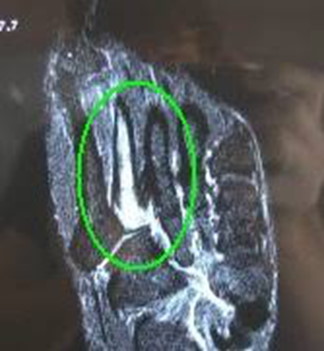

To get a better understanding of what is happening inside your foot, imaging tests may be necessary.

An MRI scan can detect a stress fracture in its early stages, even before an X-ray, however X-rays will often be taken first.

MRI scans are more sensitive than x-rays, which can only detect stress fractures after the healing process has begun.